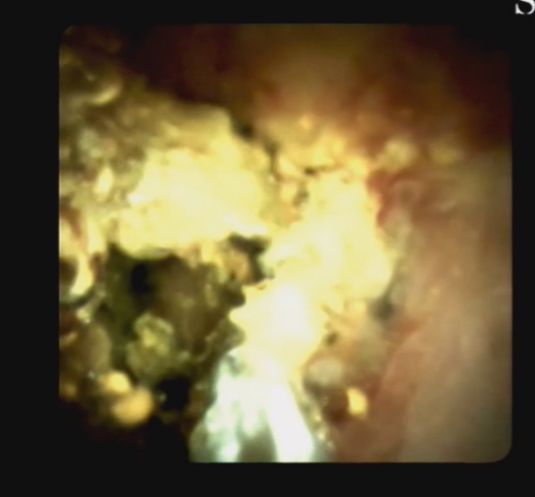

另外,經(jīng)口膽道子鏡光纖直視系統(tǒng)(SPYGLASS)是一種電子膽道子鏡,可通過十二指腸鏡到達(dá)膽管或胰管內(nèi),對病變進(jìn)行直視觀察,高清高分辨率顯示病變、并精準(zhǔn)指導(dǎo)活檢,對于膽胰管狹窄的診斷治療具有重要意義。

5466bc1aa2b44eeabb2f6ab4904c0f6c.Png  0c9bb25f31ed492197b787eecbde3974.Png

經(jīng)口膽道鏡下膽總管碎石